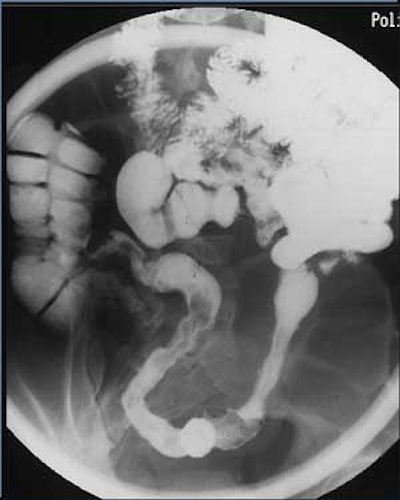

![]() |

| Conventional enteroclysis of the same patient shows inflammatory contour irregularities of the mucosal relief in the region of the Bauhini's valve and the terminal ileum; presence of a fistula was suspected. Additionally, there is a stenosis of the preterminal ileum with dilatation of the prestenotic loop. |